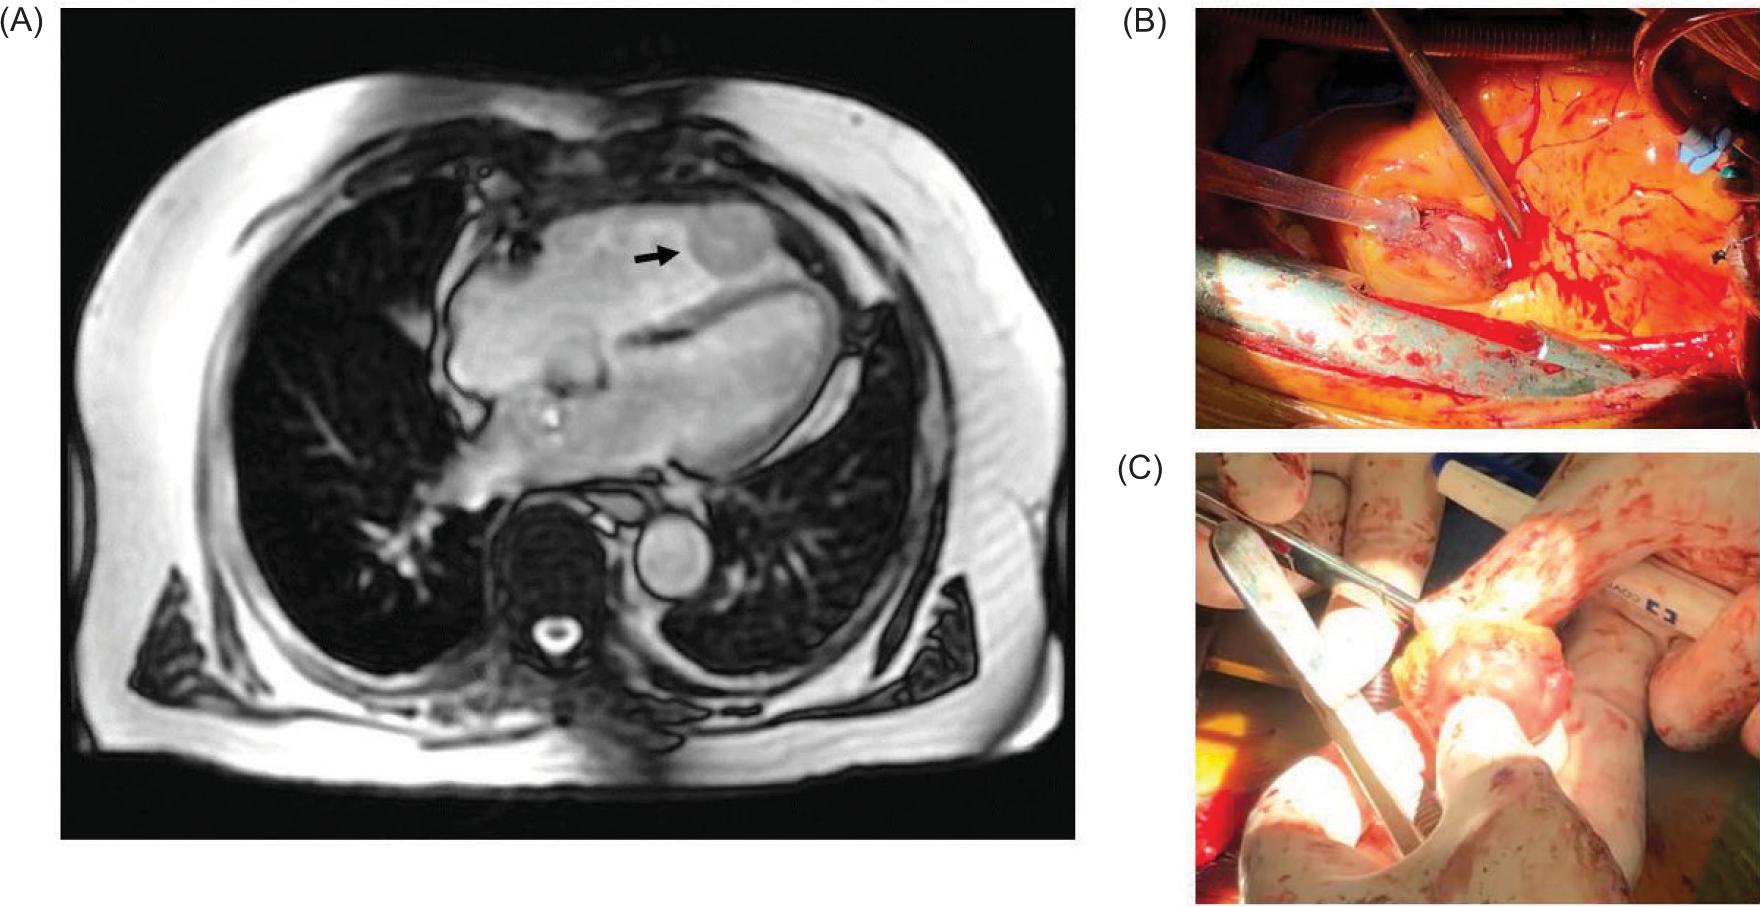

Informed consent was obtained in accordance with the Office of Research. A 65-year-old male presented with an incidental finding of a right renal mass. He underwent right radical nephrectomy, and pathology showed clear cell RCC (ccRCC) pT3a with negative margins. The nephrectomy specimen was not sent for genomic testing. Twelve years later, he presented with progressive dyspnea and unintentional weight loss. Computed tomography and echocardiogram demonstrated a right ventricular apical mass measuring 3.5 × 3.3 cm in size (Figure 1). He underwent right ventricular tumor resection. Intraoperatively, the tumor was found to be attached to the right ventricular free wall, which was excised through circumferential excision. Pathology showed metastatic ccRCC. Immunohistochemistry was positive for PAX8, RCC antigen, and CD10, whereas it was negative for CK7, CK20, CD117, and epithelial membrane antigen (EMA).

Figure 1: A 77-year-old male with delayed isolated cardiac metastasis from renal cell carcinoma; (A) Computed tomography demonstrating an enhancing, circumscribed T2 hyperintense T1 isointense right ventricular mass at the ventricular apex measuring 3.5 × 3.3 cm (arrow); (B) Intraoperative image showing the cardiac metastasis identified in the right ventricular wall; (C) Intraoperative image showing the final resected specimen sent for targeted sequencing. A VHL mutation was identified c.494T > G (p.V165G) in exon 3 in 41% of 241 reads.